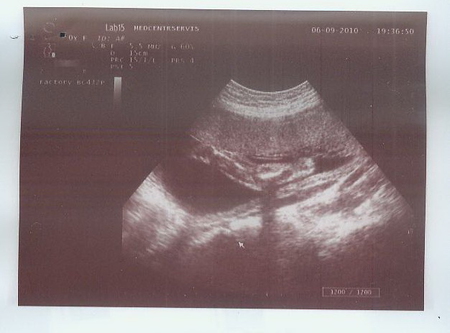

А вот и фото:

2) Ручка полусогнутая, сжатая в кулачок :)